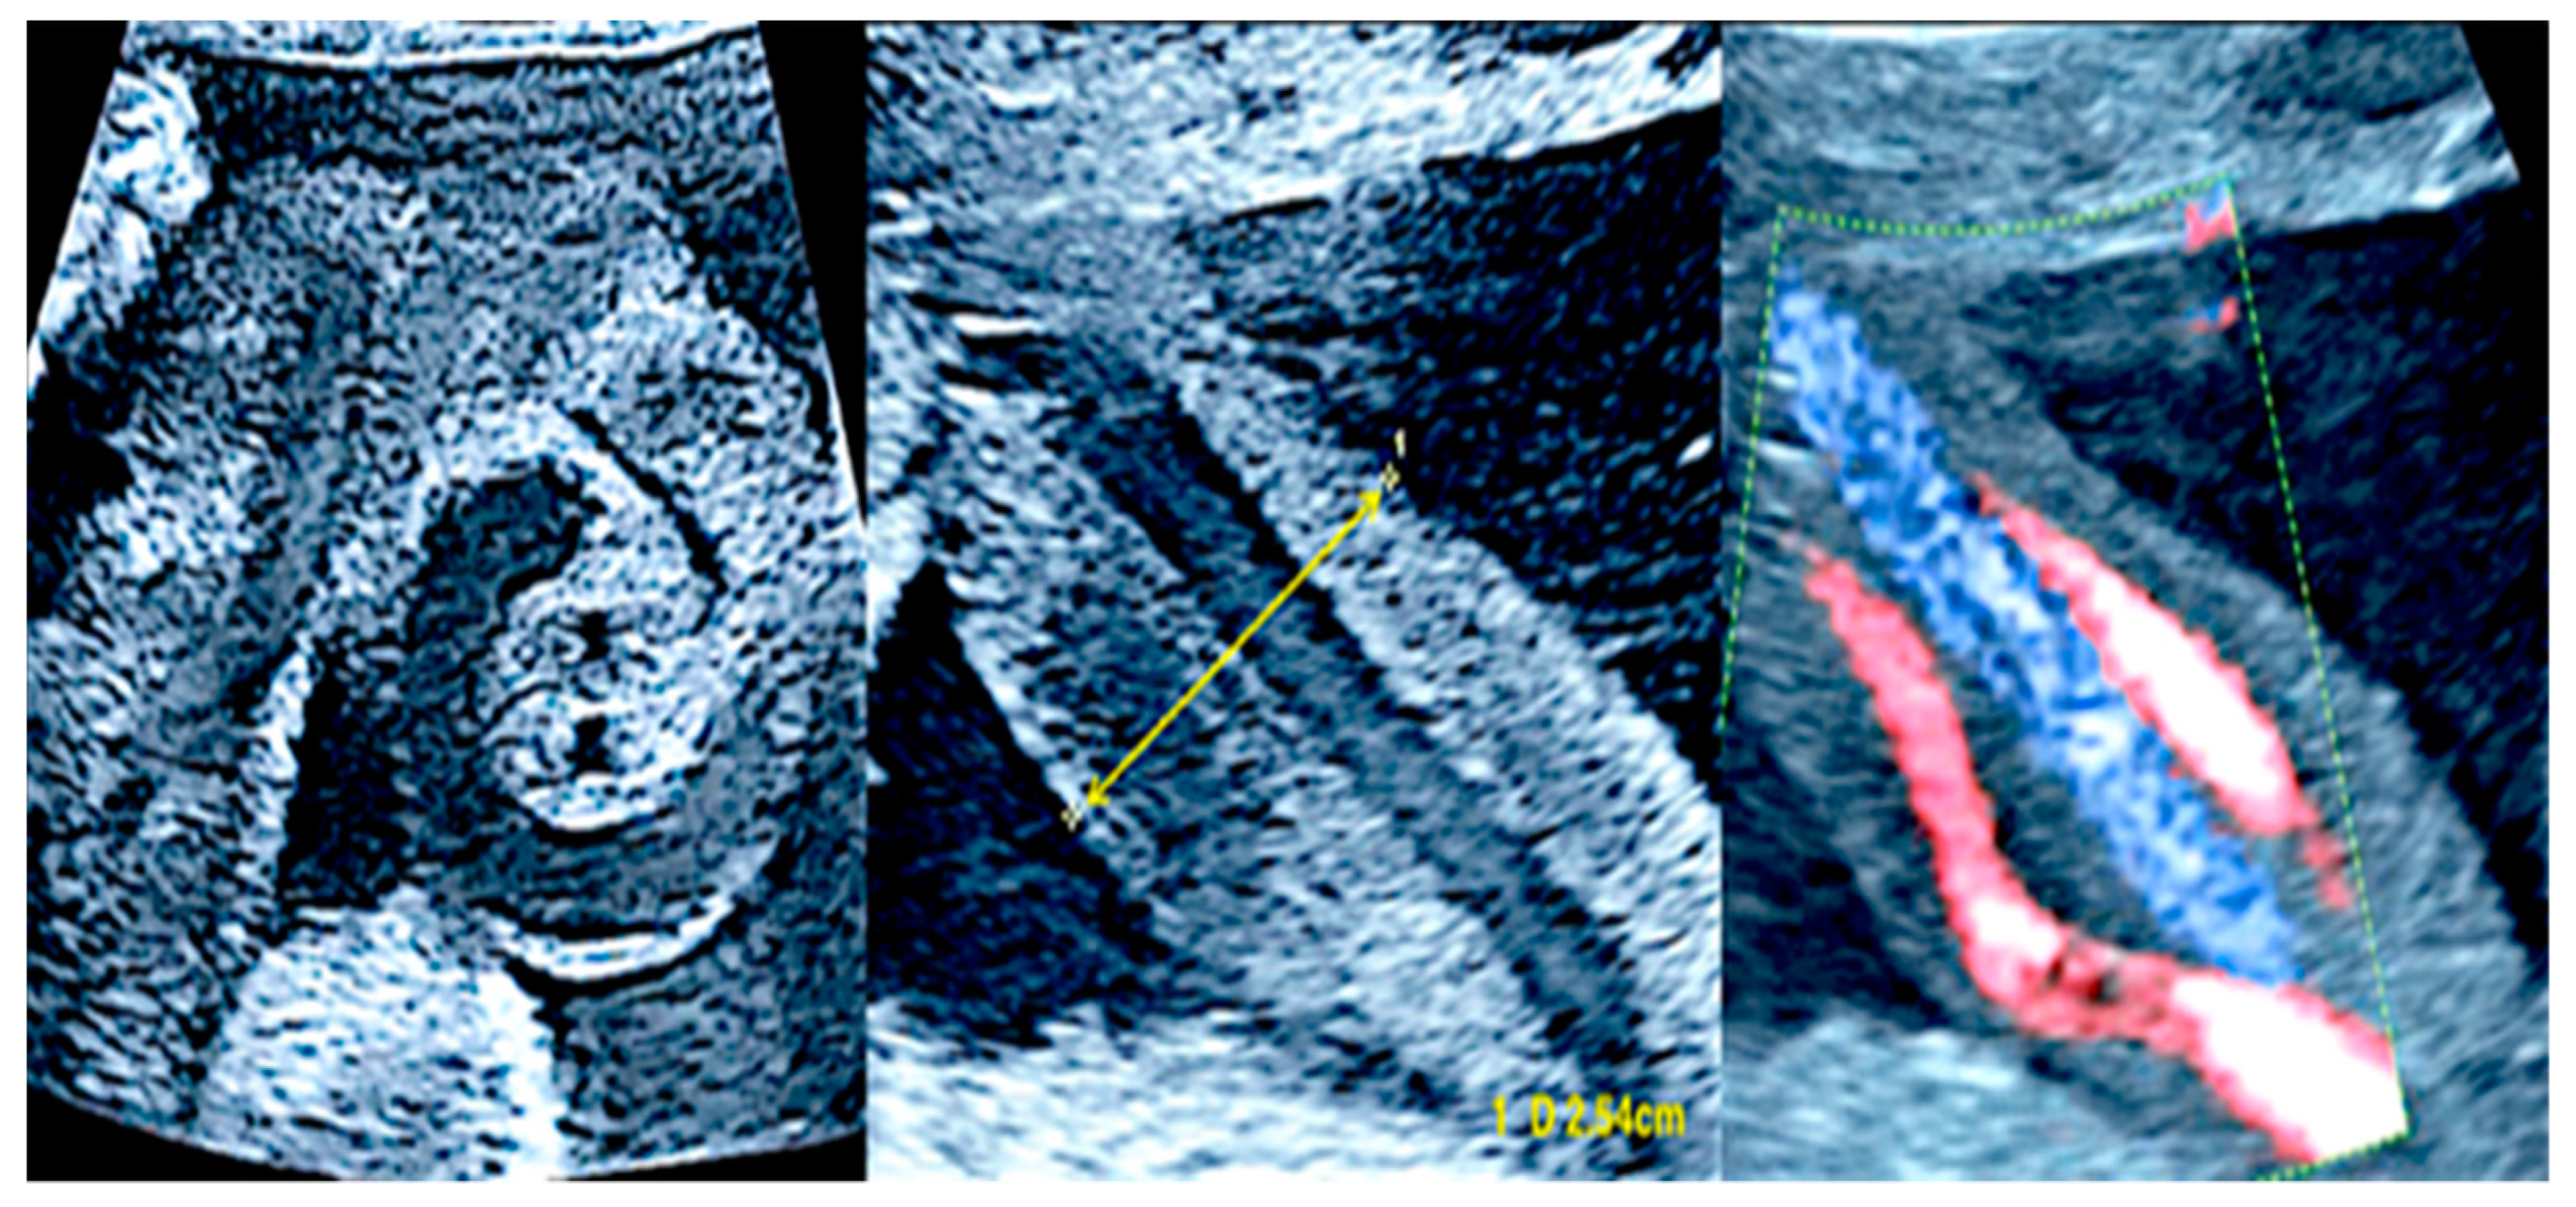

3.1. Cord Coiling